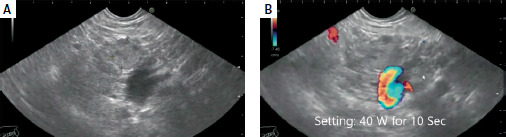

Material and methods: This prospective study included 27 patients, 15 males and 12 females, with a mean age of 36.38 years. EUS-RFA was carried out in 13 patients; 11 had pancreatic insulinoma, and 2 had advanced pancreatic adenocarcinoma. The mean size of the masses was 20.6 mm, while that of the insulinomas was 17.4 mm. The median number of needle passes was 3, with a range of 1 to 6. RFA was conducted using 19G EUSRA needles from Taewoong Co., Ltd., South Korea. No minor or major complications were observed. EUS-EA was carried out in 14 patients, all of whom had pancreatic insulinoma. The mean size of the masses was 15.3 mm. The median number of needle passes was 2, with a range of 1 to 3. We used 19G and 22G echo tip FNA needles from Cook Company, USA. The mean duration of follow-up was 12.4 months. There was mild to moderate acute pancreatitis in 4 patients in the EUS-EA group; all were relieved by conservative therapy, and no hospital admission was required. No early or late significant complications were reported in the EUS-RFA group.